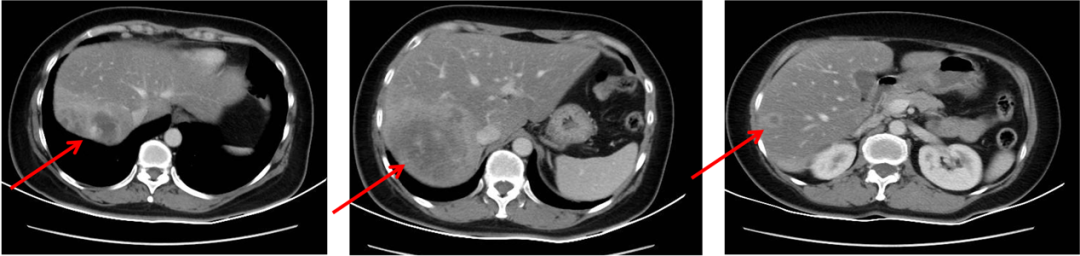

▌三线治疗:

入组MO28231临床试验,于2016-12-1开始行T-DM1治疗,具体:T-DM1 3.6mg/kg 237.6mg d1,Q21d。最佳评效PR。肝门区淋巴结自2019-6出现,逐渐增大,2019-11增大至29*22mm,考虑转移,判定为新发病灶PD出组,共治疗48周期,PD时间为2019-6,PFS为30月。不良反应:胆红素升高1级,血小板下降1级,疲劳1级,鼻出血1-2级,关节僵硬1级,手足麻木1级。

图4. 三线治疗